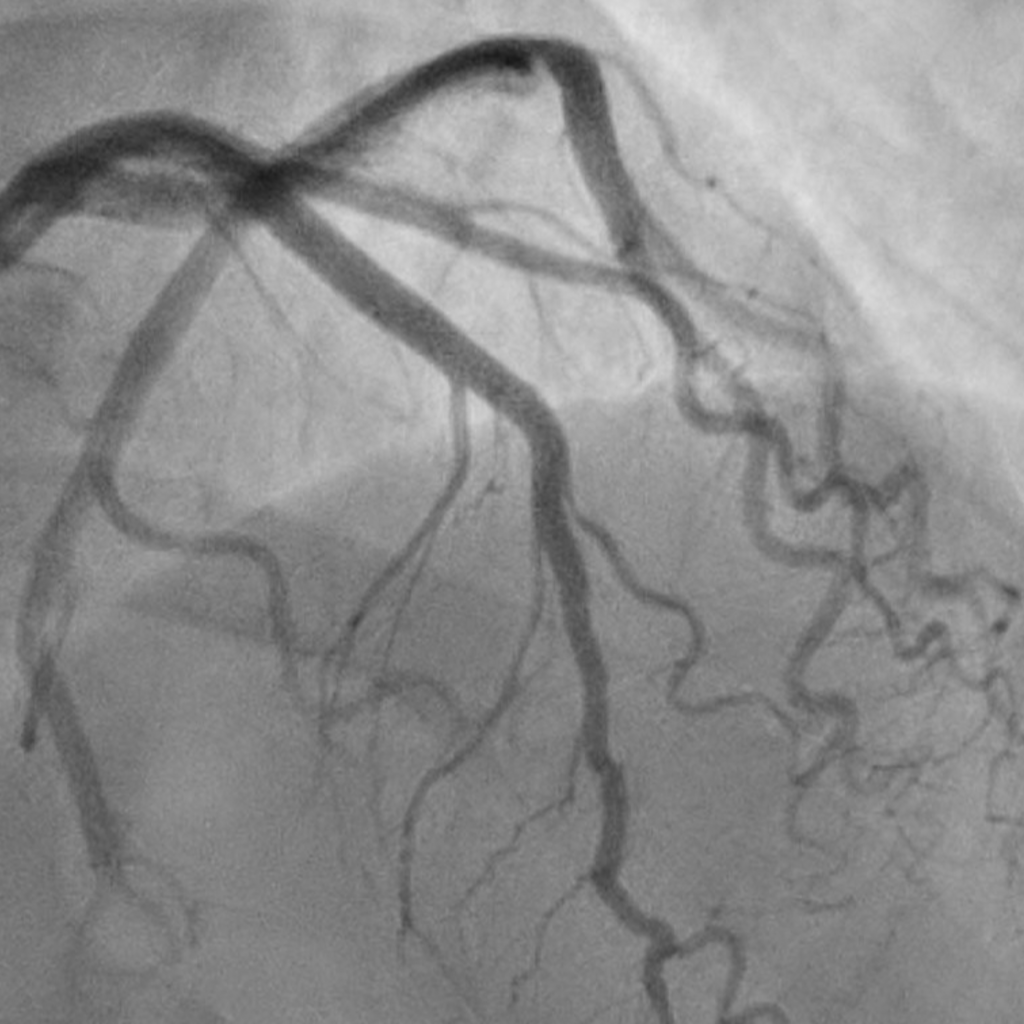

Radiopaque Aptamer Dimers as Next-Generation Contrast Agents

Identification of key regulators of atherosclerosis regression

Developing Novel Radiopaque Aptamer Dimers (RADs) as a Next-Generation Contrast Agent